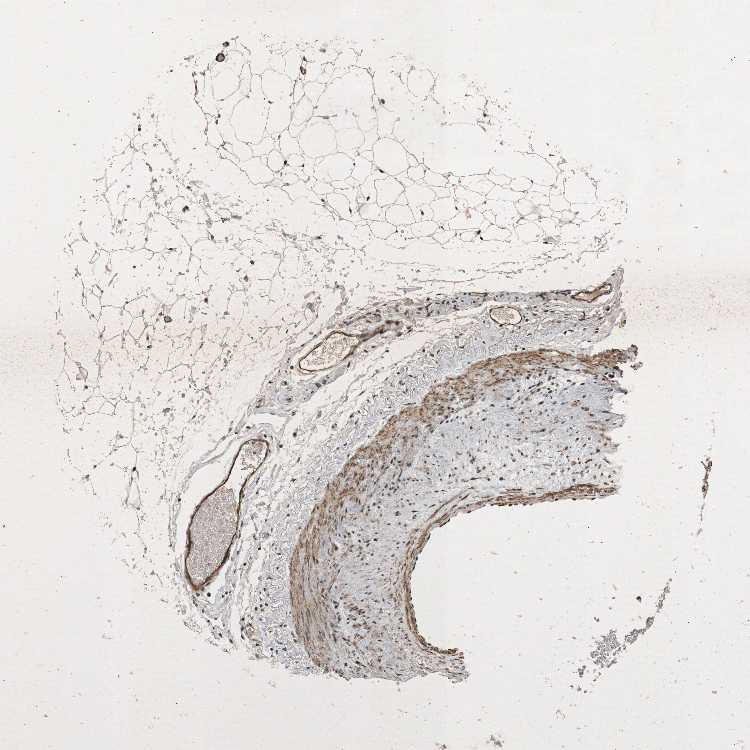

TISSUE PRIMARY DATA SOFT TISSUE Show tissue menu

SOFT TISSUE - Expression summary

SOFT TISSUE 1 - Antibody stainingi

Antibody staining in the annotated cell types in the current human tissue is reported as not detected, low, medium, or high, based on conventional immunohistochemistry profiling in selected tissues. This score is based on the combination of the staining intensity and fraction of stained cells.

Each image is clickable and will lead to virtual microscopy that enables deeper exploration of all samples and also displays staining intensity scores, fraction scores and subcellular localization as well as patient and tissue information for each sample.

Antibody HPA008926Antibody CAB011625

Chondrocytes -Medium

Fibroblasts HighMedium

Peripheral nerve -Medium

SOFT TISSUE 2 - Antibody stainingi

Fibroblasts MediumMedium

Peripheral nerve MediumMedium